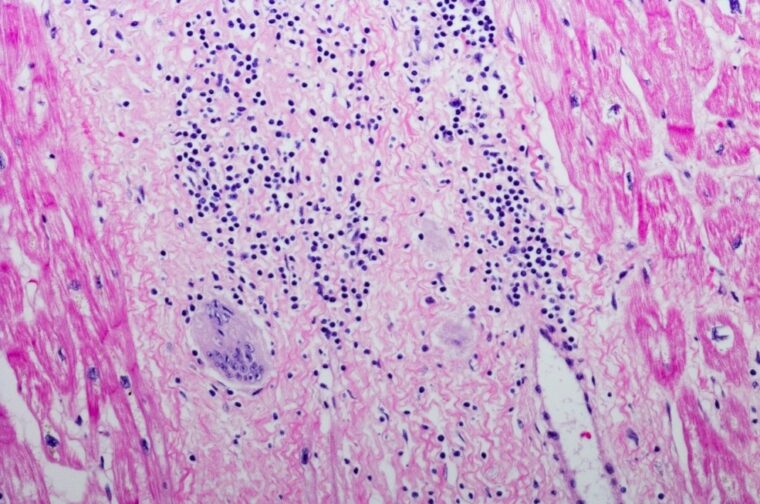

Granulomi se razvijejo v vseh prizadetih organih in tkivih, sestavljajo pa jih epiteloidne celice. V samem procesu sanacije vnetja pri nekaterih bolnikih granulomi izginejo, medtem ko pri drugih fibrozirajo, zaradi česar je lahko obsežna pljučna sarkoidoza tudi vzrok za nastanek pljučne fibroze. Ozadje tega prav tako ni povsem pojasnjeno, kot tudi vzročnost bolezni same.

Vnetje sčasoma poškoduje organe in zmanjšuje kakovost življenja posameznika, bolezen pa ne vpliva le na telesno zdravje, temveč tudi na vsakdanje življenje. Bolniki pogosto poročajo o zmanjšani telesni zmogljivosti, težavah pri opravljanju dela ter občutku, da ne zmorejo več vsega, kar so nekoč. Zanesljivih pokazateljev, ki bi napovedali potek bolezni, ni, prav tako ne poznamo zdravljenja, ki bi odpravilo njen vzrok. Za potrditev diagnoze nista dovolj le pogovor z bolnikom in rentgenska slika pljuč. Zdravnik mora z odvzemom vzorca tkiva dokazati značilne vnetne spremembe (t. i. granulome) ter hkrati izključiti druge bolezni, ki lahko povzročajo podobne spremembe, predvsem tuberkulozo in glivične okužbe.